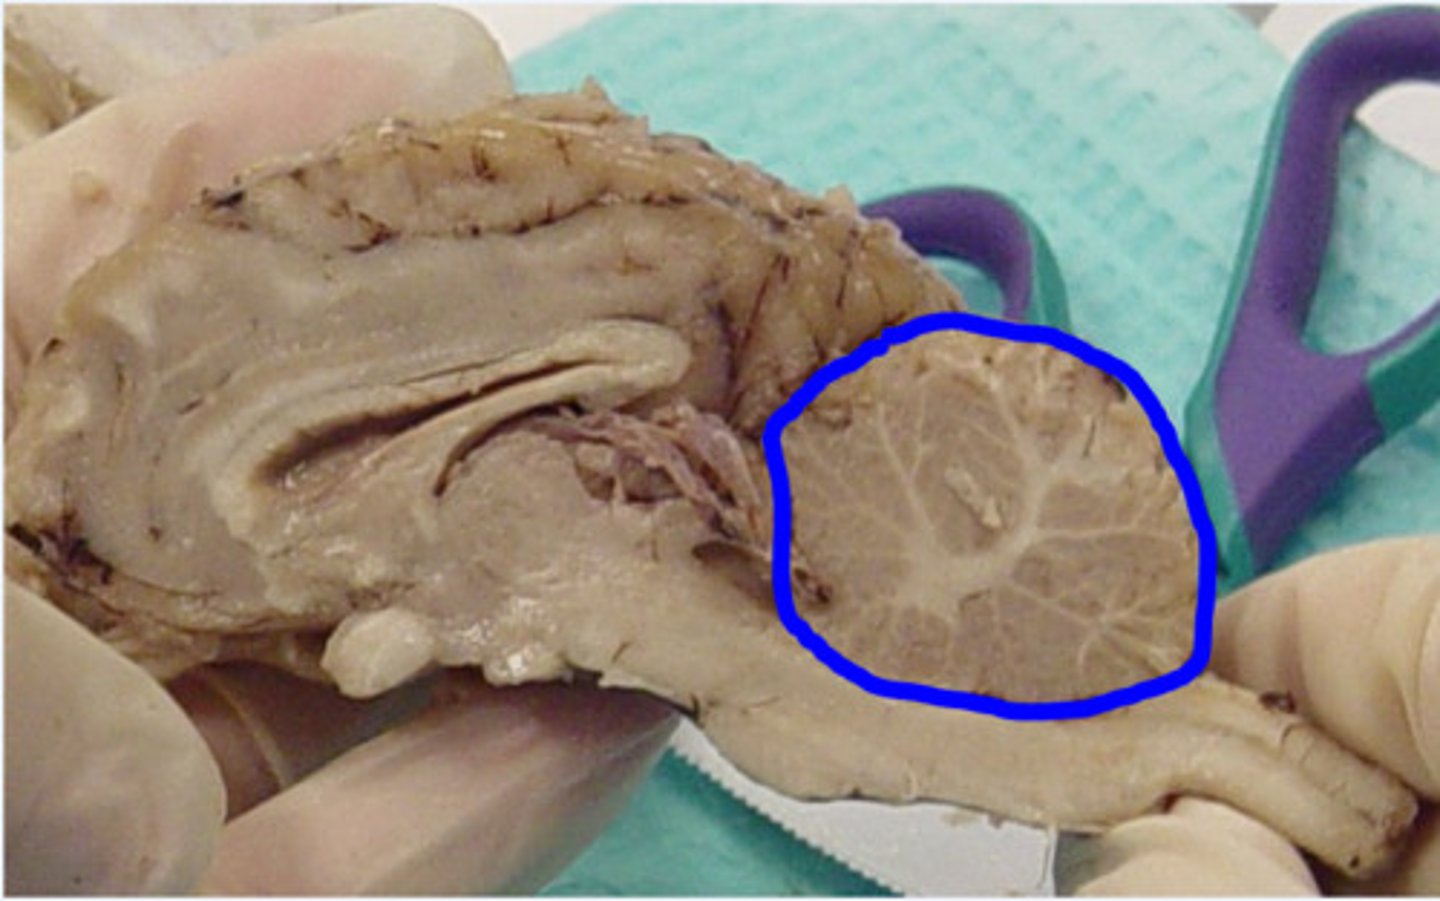

Arbor vitae

What is this?